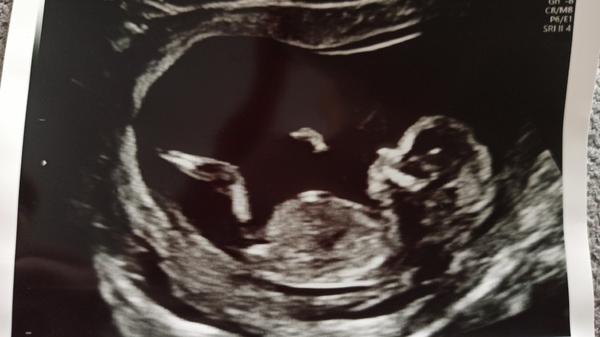

11+5 utz - je to holka. Mám s tím počítat?

Vzhledem k tomu, že v tomto období se pohlaví teprve dotváří, tak bych to spíš viděla jako věštění ze skleněné koule 🙂 Ale přání otcem myšlenky...

Holku nepoznali ani na NT screeningu ve 14tt, to bylo vyloženě 50:50, chvíli to vypadalo tak, chvíli tak. Já bych počkala.

@monii007 vyčkala bych minimálně do druhého screeningu. Nám takhle v 14tt řekli kluka a je to jistě holka, podstoupila jsem geneticke vyšetření a to je 100%. Na druhém screeningu v 23tt potvrzena holčička.

Ještě bych počkala, nám řekli ve 14tt, že to vypadá asi na holku, ale potvrdili nám to až ve 20tt

@monii007 🙂. Ten prvni screening je fakt odhad, kde se hlavne resi, kam smeruje ten hrbolek, coz muze byt dost zavadejici... mne treba na 1.i odmitli rict odhady, ze to nedelaji... Na druhem uz jsou narostle pohlavni organy, cili pokud je tam dobre videt, vetsinpu uz se to da rict presne...